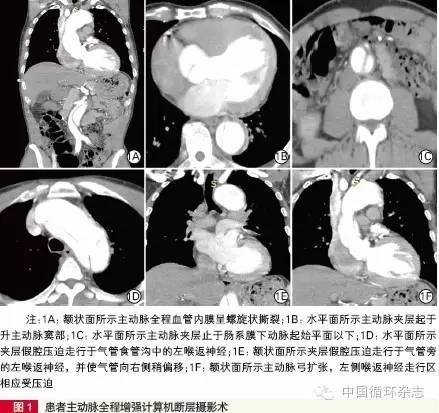

入院后心电图示:窦性心律,左心室高电压。急诊行主动脉全层增强计算机断层摄影术血管造影(CTA,图1)。

图1 可见:(1)AD(Stanford A 型),累及左右冠窦。升主动脉瘤。(2)颈部大血管均受累。(3)腹腔干起始处管腔狭窄,近段内膜撕裂并呈瘤样扩张。(4)右肾双肾动脉供血。左肾动脉起自假腔,左肾灌注减低,左肾囊肿。